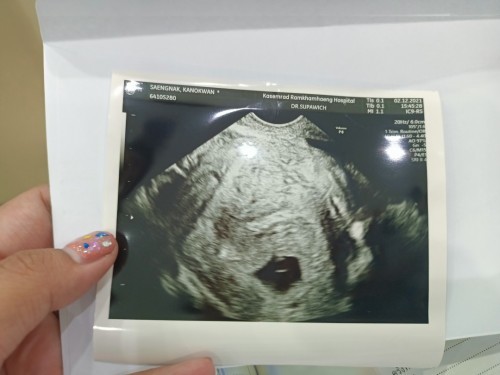

เค้า 2 เดือนค่ะ

7 เกือบ 8 วิคค่ะ